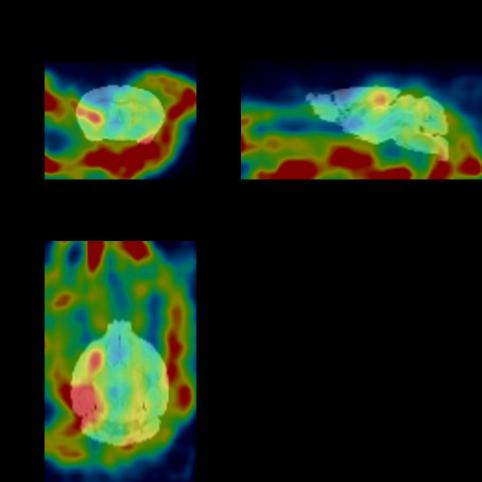

下(xià)圖為(wèi)30min顯像圖像